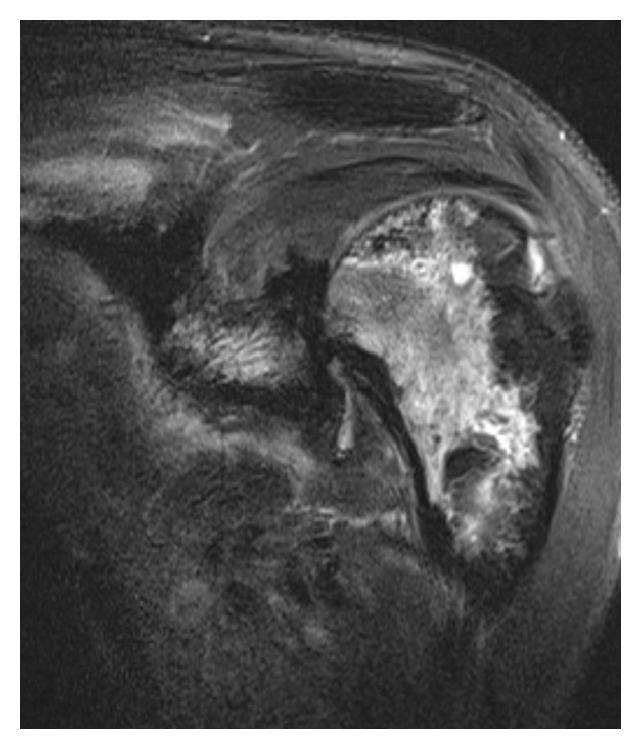

Progressive Diffuse Osteonecrosis in a Patient with Secondary Hemophagocytic Lymphohistiocytosis.

Case Rep Radiol. 2015;2015:730719. doi: 10.1155/2015/730719. Epub 2015 Nov 29.